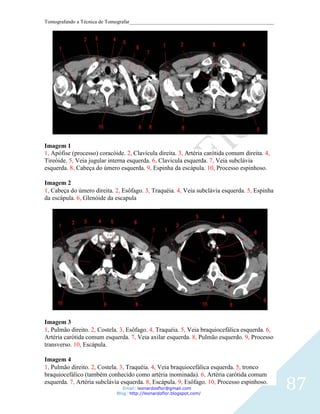

Imagem 1

Corte axial. 1, Cavidade orbitária. 2, Seio frontal. 3, Osso esfenóide

Imagem 2 - Corte axial. 1, Globo ocular. 2, Septo nasal. 3, Células etmoidais. 4, Seios

esfenóidal. 5, Hipófise. 6, Dorso sellae.

Imagem 3

Corte axial. 1, Globo ocular. 2, Septo nasal. 3, Células etmoidais. 4, Seios esfenóidal. 5,

Clivus.

Imagem 4

Corte axial. 1, Seio maxilar esquerdo. 2, Canal nasolacrimal. 3, Concha. 4, Septo nasal. 5,

Arco zigomático. 6, Processo condilar da mandíbula.

Imagem 5

Corte axial. 1, Concha. 2, Seio maxilar. 3, Asa lateral do processo pterigóideo. 4,

Nasofaringe. 5, Atlas (C1). 6, Fenda do palato ptérigo.

Imagem 6

Corte axial. 1, Seio maxilar. 2, Apófisis pterigoides,. 3, Nasofaringe. 4, Mandíbula. 5, Arco

45

anterior do atlas. 6, dente do áxis (Processo odontoide).